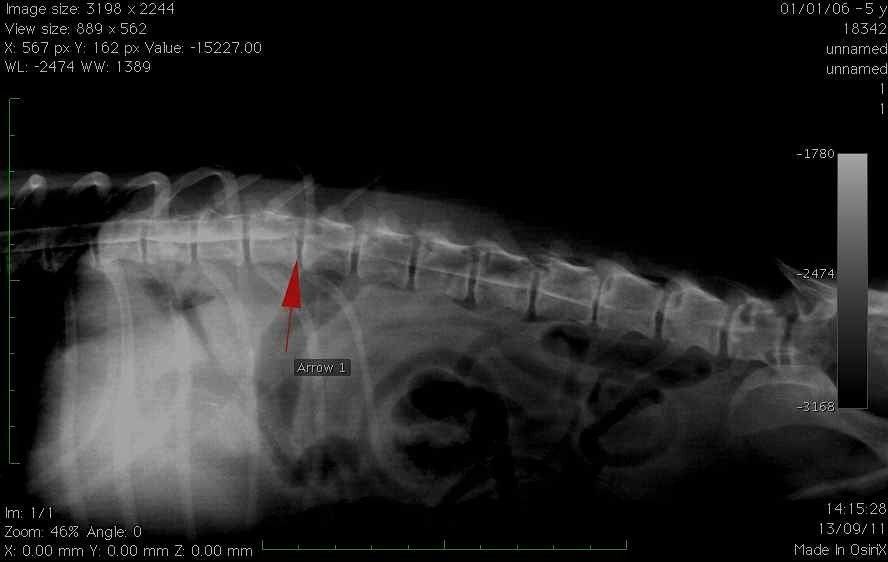

- Les chirurgies de hernie discale qui sont devenues les premières pathologies rencontrées en neurologie chez le chien.